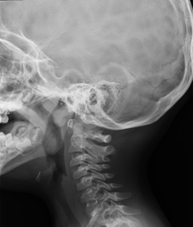

Técnica mediante la cual, utilizando rayos X, se obtienen imágenes del cuello para su estudio. Indicaciones: estudio de bultos o nódulos. - RX Charnela

Técnica mediante la cual, utilizando rayos X, se obtienen imágenes de la charnela o de la base del cráneo para su estudio. Indicaciones: estudio de malformaciones congénitas.